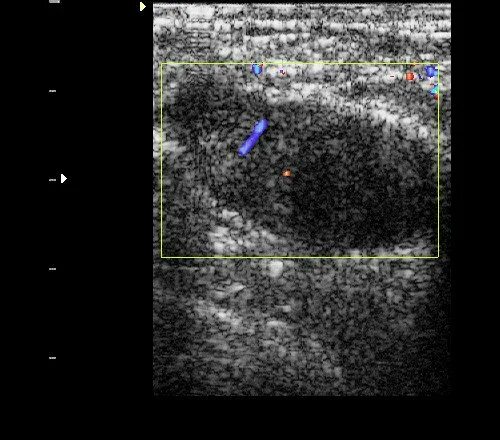

Локусы при цдк что это